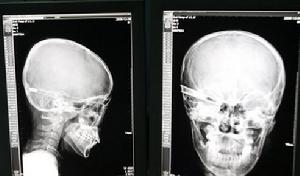

1.X線特殊檢查 計算機X線斷層攝影(CT)、磁共振成像(MRI)和數字減影(DSA)等特殊檢查腦部是確定腦部轉移性腫瘤和病灶定位的最重要檢查,其他檢查只是輔助性手段。由於血腦屏障和血腫瘤屏障的改變,經注射造影劑後其對比度加強,對疑有腦轉移者作CT檢查,約90%以上腦轉移灶可示典型的類圓形影,常位於白質和灰質結合部,其周圍還可見低密度區,為腦轉移灶周圍水腫所致。多數腦轉移灶在造影劑加強前是低密度區但黑素瘤絨癌和結腸癌的腦轉移灶為例外在造影劑加強前常呈現高密度。使用薄層檢查可發現直徑5mm左右病灶。MRI能從多種體層面觀察,並可用不同參數(T1、T2、質子密度)以增進發現異常影像並對其病變性質有一定鑑別能力。由於腦、脊髓含脂肪(即包括豐富的氫質子)成分高,成像效果好,而轉移性腫瘤含脂肪低,故常用於確定腦轉移性腫瘤是否存在,並對鑑別腫瘤、出血、腦積水、腦水腫有一定幫助。